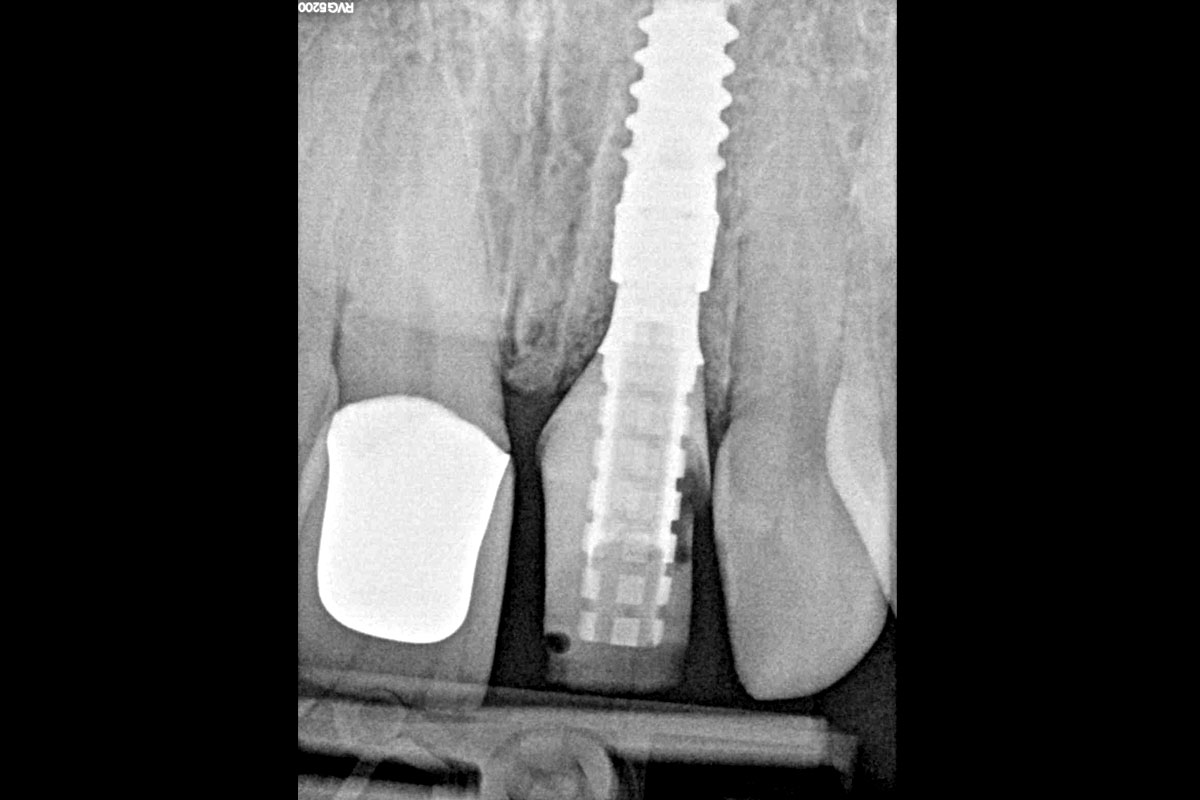

cerabone® and mucoderm® for immediate implantation in the aesthetic area - Dr. D. Robles

Initial clinical situation - Central incisors with dental destruction and periapical pathology